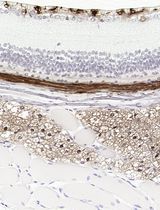

Improved Immunohistochemistry of Mouse Eye Sections Using Davidson's Fixative and Melanin Bleaching

AL Anne Nathalie Longakit

CH Chloe Hess

CZ Christina Zhang

CV Catherine D. Van Raamsdonk

1715 Views

Nov 20, 2025

Immunohistochemistry (IHC) and immunofluorescence (IF) are fundamental molecular biology techniques to assess protein expression. However, the melanin present normally in the eye in the uveal tract (choroid, iris, and ciliary body) and the retinal pigment epithelium (RPE) poses a significant challenge for IHC and IF. This is because melanin interferes with both chromogenic and fluorescent detection methods. Additionally, formalin fixation, which is commonly used for IHC, can result in shrinkage and loss of cellular detail in the eye. This protocol provides an optimized approach using Davidson’s fixative with a hydrogen peroxide bleaching step to eliminate melanin interference in the mouse eye, improving the quality and interpretability of IHC analyses of the uveal tract and RPE. It is particularly useful for the analysis of uveal melanoma.